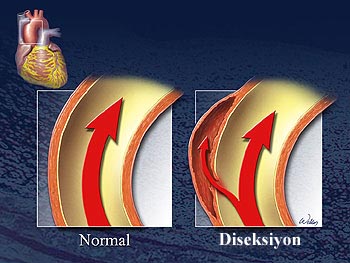

Aort Diseksiyonu

Aort duvarının 3 ana katmanı vardr. Aortanın iç katmanının yırtılarak kanın orta katmana geçmesine ve burada yeni bir lümen oluşturmasına aort diseksiyonu denilmektedir. Genellikle yaşlı insanlarda görülür. Yeni oluşmuş aort diseksiyonu acil ve hayatı tehdit eden bir durumdur. Aortanın dış katmanının da yırtılarak patlama ihtimali vardır. Hastaların %50’si ilk 48 saatte ölür. Daha sonraki her saatte ölüm riski %1 artar. Tıbbi tedavi ile hastaların %58’i kaybedilir. Aortanın patlaması halinde hayatta kalma şansı azalır.

Yerleşimlerine göre aort diseksiyonu tipleri

Yapay damarla aort diseksiyonu tamiri. Bu tür ameliyatlarda kalp akciğer makinesi kullanılarak hastanın vücut sıcaklığı 19?C’ye kadar soğutulmakta ve ameliyat bitinceye kadar dolaşım tamamen durdurulabilmektedir.